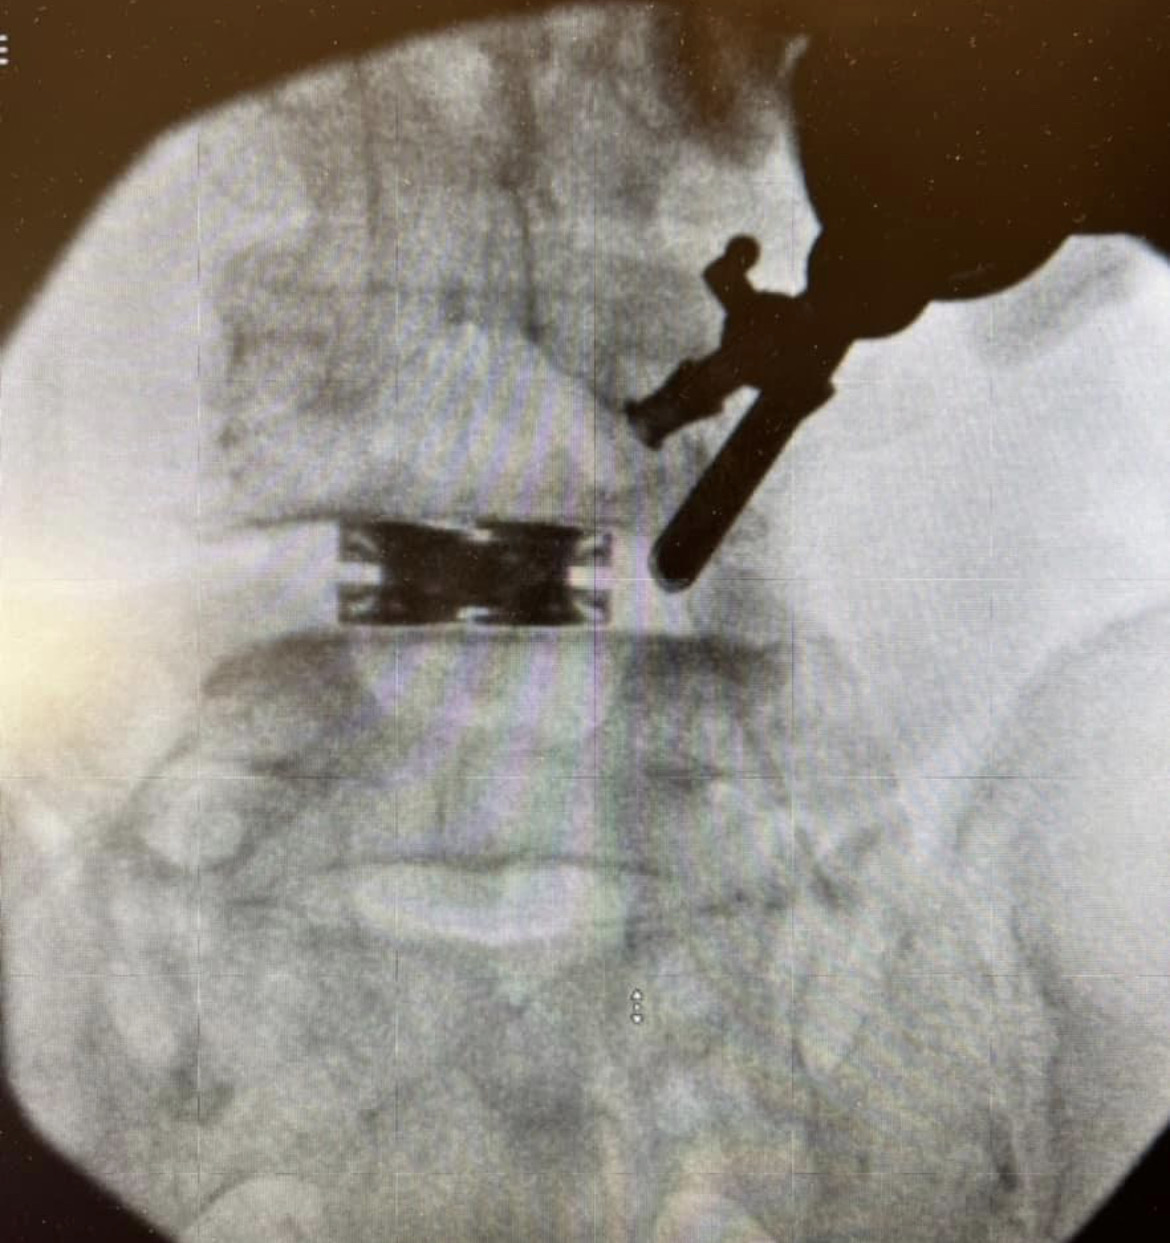

dualX®Slim transforms the fusion environment from insertion to spinal restoration by delivering a powerful dual-expanding implant through a minimally-invasive or endoscopic approaches. dualX®Slim has one of the smallest insertion profiles in the market while still expanding in both horizontal and vertical directions to provide an ALIF-sized final geometry with higher degrees of lordosis (8°, 12°, 15°, 18°*) through the patented trueLordosis™ technology.

Lateral expansion establishes stable footprint Large, center bone graft chamber for post-expansion grafting

20 mm Fully Expanded Width

Powerful vertical expansion restores disc height for decompression

Vertical expansion assists in direct and indirect decompression Multiple lordotic angles restore sagittal balance